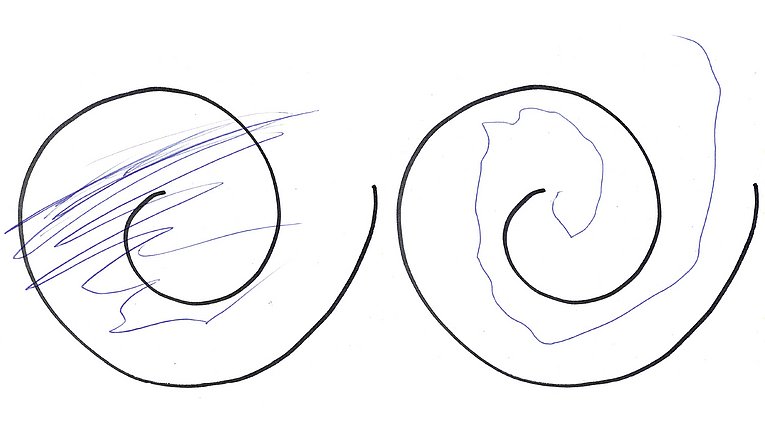

Das Umfeld von Irene F. zeigte sich zunächst skeptisch – ein chirurgischer Eingriff am Kopf stellt schließlich immer ein gewisses Risiko dar und löst häufig Ängste aus. Doch die 71-Jährige war sofort überzeugt. Dass sie sich beim Behandlungsteam um Dr. Regensburger und Dr. Schmidt gut aufgehoben fühlte, bestärkte ihren Entschluss. „Ich habe mich richtig auf die Operation gefreut“, sagt sie und lacht. „Eine THS ist ein Eingriff in zwei Etappen: Zunächst findet eine mehrstündige Operation am Kopf der wachen Patientin statt – das Gehirn selbst empfindet keine Schmerzen; danach folgt ein kurzer Eingriff am Schlüsselbein unter Vollnarkose“, erklärt Dr. Schmidt. Vor allem der erste Abschnitt erfordert höchste Präzision: Die haarfeinen Elektroden werden mittels eines computerassistierten Zielführungssystems – der sogenannten Stereotaxie – millimetergenau an zwei zuvor definierte Punkte im Gehirn geleitet. Nur, wenn sie dort exakt platziert werden, ist ein Effekt zu erwarten; schlimmstenfalls können Schluckstörungen oder andere unerwünschte Nebenwirkungen auftreten. „Das Zielgebiet ist in etwa so groß wie ein Reiskorn“, sagt die Neurochirurgin. Dass die Patientin dabei wach ist, ist von entscheidendem Vorteil. Denn durch verschiedene Tests, etwa das Nachzeichnen von Linien mit einem Kugelschreiber oder das Ausstrecken der Arme, kann das Operationsteam bereits während des Eingriffs beobachten, ob der Tremor nachlässt. „Bei Frau F. benötigten wir nur wenige Anläufe, bis wir das gewünschte Ergebnis erreichten“, berichtet Dr. Regensburger. „Im zweiten Teil konnte dann der Impulsgenerator, sozusagen die Batterie des Gehirnschrittmachers, planmäßig neben dem Schlüsselbein implantiert und mit den Elektroden im Gehirn verbunden werden.“